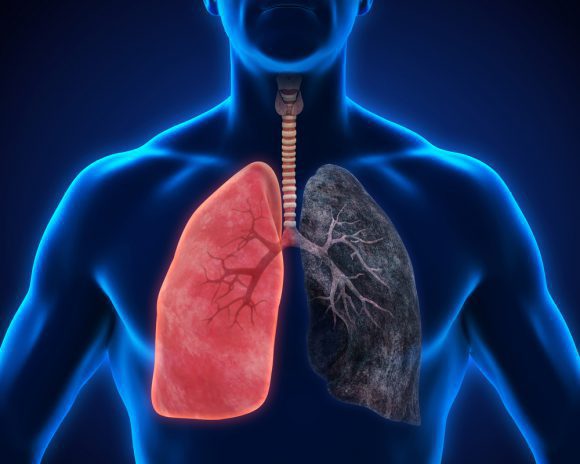

둘째, 환경적 요인이 '폐암'으로 이어질 수 있습니다. 일상 생활에서 흡입되는 발암 물질은 폐암을 유발할 수 있습니다. 즉, 대기오염 가스 중의 발암물질을 흡입하거나 흡연을 통한 발암물질을 직간접적으로 흡입함으로써 폐암이 발생할 수 있습니다. 흡연은 폐에 매우 치명적이어서 흡연은 폐암의 가장 큰 원인이며, 비흡연자도 간접흡연으로 폐암에 걸릴 수 있습니다.

이러한 폐암의 원인으로 인해 폐암으로 진단되기 전에 폐암 초기증상을 조기에 발견하면 다른 장기로의 전이나 진행성 폐암으로의 진행을 어느 정도 지연시키거나 적절하게 치료할 수 있지만 일반적으로 폐암의 초기 단계는 특별한 징후나 증상이 없으므로 조기에 발견하는 경우는 극히 드뭅니다.